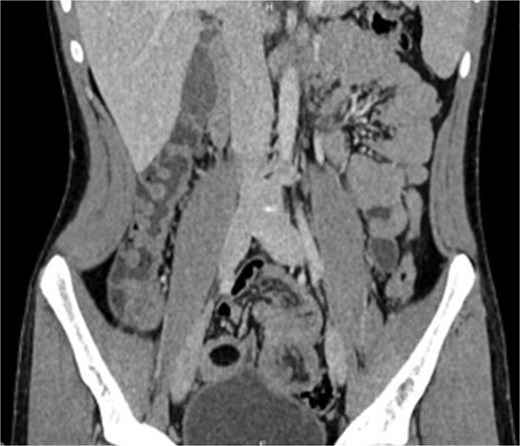

Laboratory findings were within normal ranges. Abdominal CT revealed a telescoping intestine measuring 20 × 4 cm, with an intraluminal lesion displaying fat-density at 15 × 25 mm (Fig. 1), surrounded by the thick-walled intussuscipiens (Fig. 2). No significant proximal bowel dilation or additional lesions were observed.

Axial CT scan showing an oval fat density mass representing a jejunal lipoma (A) and a telescoping intestine measuring 20 × 4 cm (B).

These findings led to a diagnosis of intussusception induced by a jejunal lipoma.